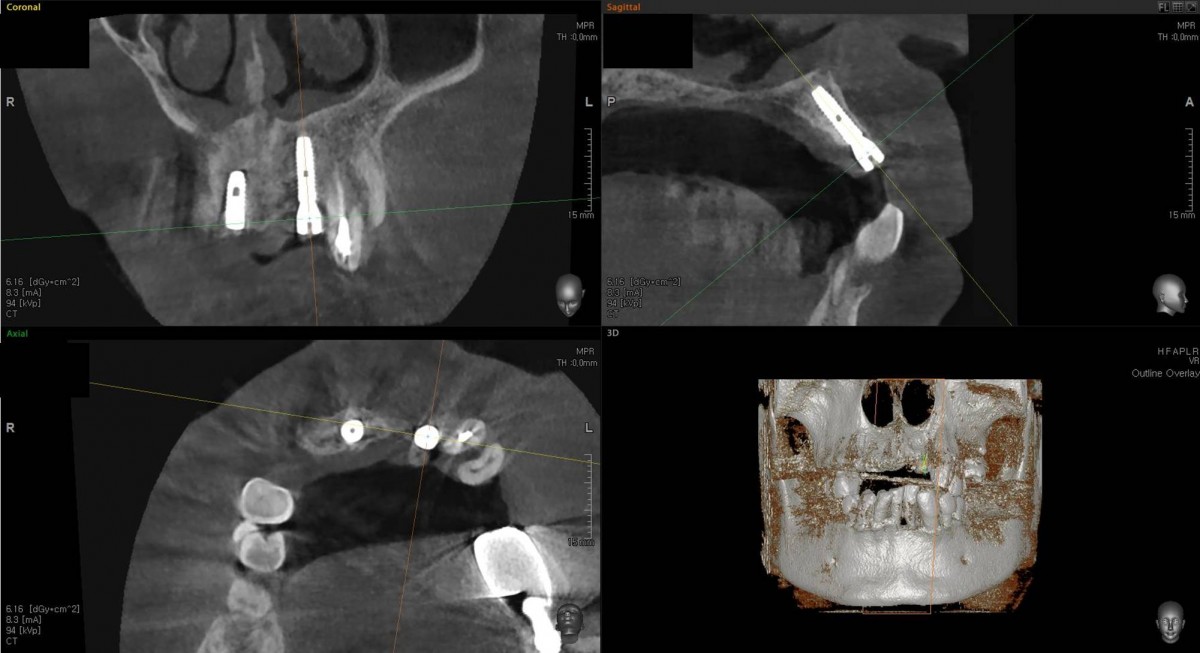

In the anterior maxilla, implant-supported fixed partial denture.

<GCpbc> A 58-year-old male is a patient undergoing implant installation in various parts. The old Br of the anterior maxilla has fallen

off and it is no longer possible to maintain it even temporarily, so a

treatment plan for the anterior teeth was made.